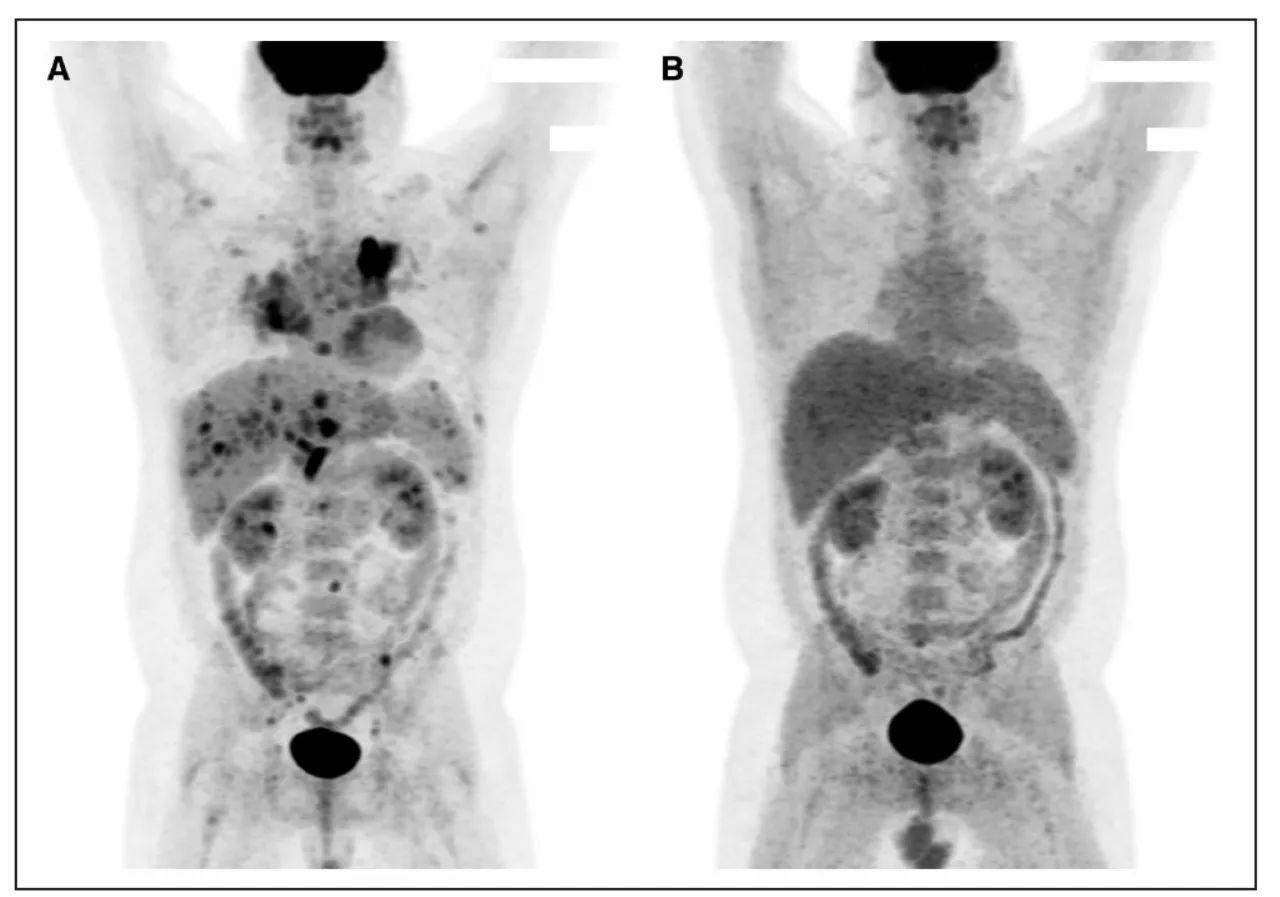

结节病 PET-CT

A.全身多部位FDG高代谢病灶:心脏,支气管周围血管,肝门,盆腔,腹股沟淋巴结,肝脾和骨骼;B. 激素治疗6个月后,高代谢病灶消失

18F-FDG PET:左室侧壁基部摄取